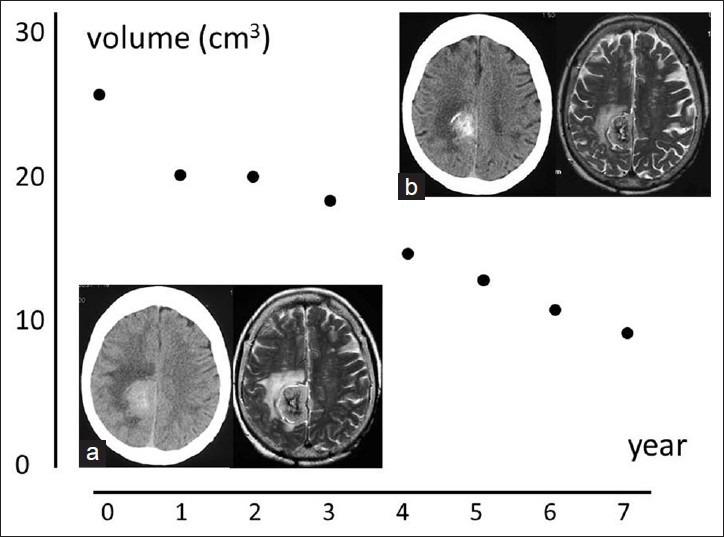

A right falx meningioma was incidentally diagnosed and was followed at every one-year by magnetic resonance imaging (MRI) for over 7 years. The tumor, with a maximum diameter of 4 cm, showed a slightly high density and was enhanced on computed tomography (CT), and a high intensity with a low-intensity core on T2 MRI, with significant edema. The meningioma gradually shrank together with a decrease of edema and increase of calcification. The initial volume, 25.5 cm(3), regressed linearly to less than half, 9.9 cm(3).

Here, we report a case of an incidentally diagnosed meningioma that regressed spontaneously. The pattern of the regression was similar to that following gamma knife radiosurgery.

一例右侧大脑镰脑膜瘤被偶然诊断出,随后通过磁共振成像(MRI)每年随访一次,持续了7年多。该肿瘤最大直径为4 cm,在计算机断层扫描(CT)上显示为略高密度且有强化,在T2加权MRI上呈高强度且有低强度核心,伴有明显水肿。脑膜瘤逐渐缩小,同时水肿减轻、钙化增加。初始体积为25.5 cm³,呈线性消退至不到一半,即9.9 cm³。

在此,我们报告一例偶然诊断出的脑膜瘤自发消退的病例。其消退模式与伽玛刀放射外科治疗后的模式相似。